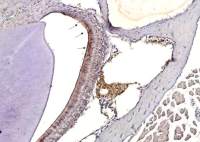

Immunofluorescence staining of VZV IE62 protein in VZV-infected MRC-5 cells by using anti-VZV gE antibody (clone #9). Anti-VZV IE62 antibody was used at 1/100 dilution. As second antibody, Alexa Fluor 488 donkey anti-mouse IgG [H+L] was used at 1/200 dilution. Nuclei were stained with Hoechst 33342.